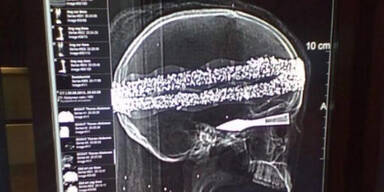

Dass der Fall nicht schon bei einer Computertomografie geklärt wurde, sei darauf zurückzuführen, dass das Plastikskelett wohl mit einer noch unbekannten Substanz besprüht wurde. Rechtsmediziner hatten bei der Untersuchung tatsächlich Knochen entdeckt, konnten laut Gaebel aber nicht erkennen, dass sie aus Plastik waren. Noch Anfang September hatte Gaebel zu dem Fall gesagt: "Nach ersten Untersuchungen gibt es Hinweise, dass die Mumie 2000 Jahre alt ist."

Der Schädel sei dagegen echt. "Es handelt sich vermutlich um einen Präparationsschädel, der zu medizinischen Ausbildungszwecken genutzt wird", sagte der Staatsanwalt. Der Schädel solle noch weiter untersucht werden, ansonsten sei der Fall für die Ermittler nun abgeschlossen. Bei einer in dem Kopf steckenden Pfeilspitze handle es sich um ein Kinderspielzeug.